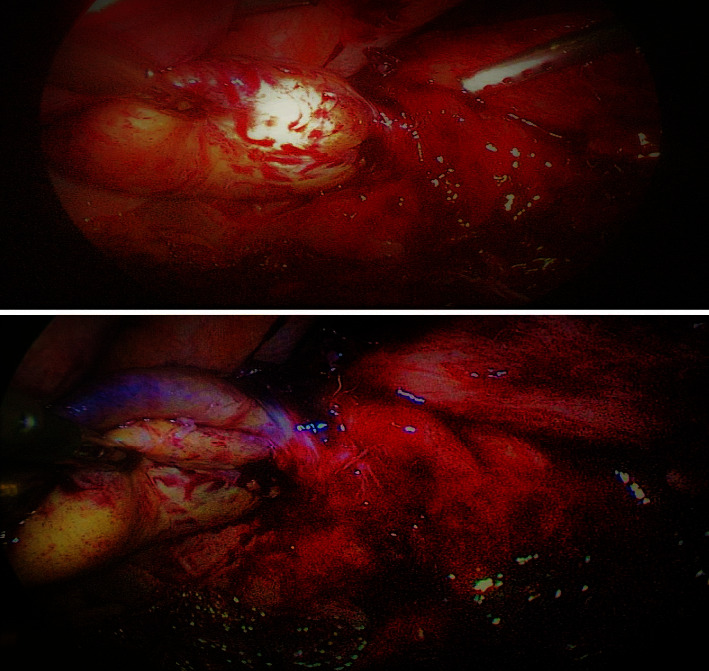

背景:胆囊肿胀是指胆囊沿胆囊管和胆囊动脉的轴线在其系膜上旋转。许多因素被认为是导致胆囊肿胀的原因,如解剖、机械、生理和荷尔蒙风险因素,但存在膨胀的胆囊和多余的系膜被认为是一个重要原因。病例介绍:一名 68 岁的妇女因右下腹疼痛和呕吐就诊,疼痛和呕吐已持续 2 天,并向肩胛间区域放射,还伴有恶心和呕吐。患者无黄疸,腹部检查显示右上腹触诊时有严重压痛并伴有戒备,但未触及肿块。白细胞升高,肝酶、胆红素和碱性磷酸酶正常。超声波检查显示有一块胆石,石壁厚度增加。服用抗生素和镇痛药后,临床症状没有明显改善。腹腔镜检查时发现胆囊肿胀,导致胆囊坏疽。患者接受了腹腔镜胆囊切除术。患者在术后第三天出院,病情明显好转,没有出现术后并发症。结论胆囊内翻是一种急性外科急症,通常见于老年人群。需要高度怀疑,尤其是在没有胆结石的情况下,并且必须与结石性胆囊炎相鉴别。大多数病例都是在手术中发现的。必须立即进行剥离和胆囊切除术,经过适当的手术干预后,大多数病例的预后都很好。

Background: Volvulus of gallbladder is defined as a rotation of the gallbladder on its mesentery along the axis of the cystic duct and cystic artery. Many factors are postulated to be the causes such as anatomical, mechanical, physiological, and hormonal risk factors but the presence of a distended gallbladder with a redundant mesentery is thought to be an important cause. Case presentation: A 68-year-old woman presented with right hypochondrial pain and vomiting for 2 days that was radiated to the interscapular region and associated with nausea and vomiting. The patient had no jaundice and the abdominal examination showed severe tenderness with guarding during palpation of the right upper abdomen with no palpable mass. The WBCs were elevated, with normal liver enzymes, bilirubin, and alkaline phosphatase. The ultrasound showed a single gallstone with increased wall thickness. There was no significant clinical improvement with antibiotics and analgesics. During laparoscopy, volvulus of the gallbladder was discovered causing gangrene of the gallbladder. Laparoscopic detorsion and successful laparoscopic cholecystectomy were performed. The patient was discharged on the third postoperative day with dramatic improvement with no postoperative complications. Conclusion: Gall bladder volvulus is an acute surgical emergency that is usually seen in the elderly population. It required a high index of suspicion especially in the absence of gallstones and must be differentiated from acalculous cholecystitis. Most cases are discovered at surgery. It must be managed with immediate detorsion and cholecystectomy, and the prognosis is excellent in most cases after an appropriate surgical intervention.